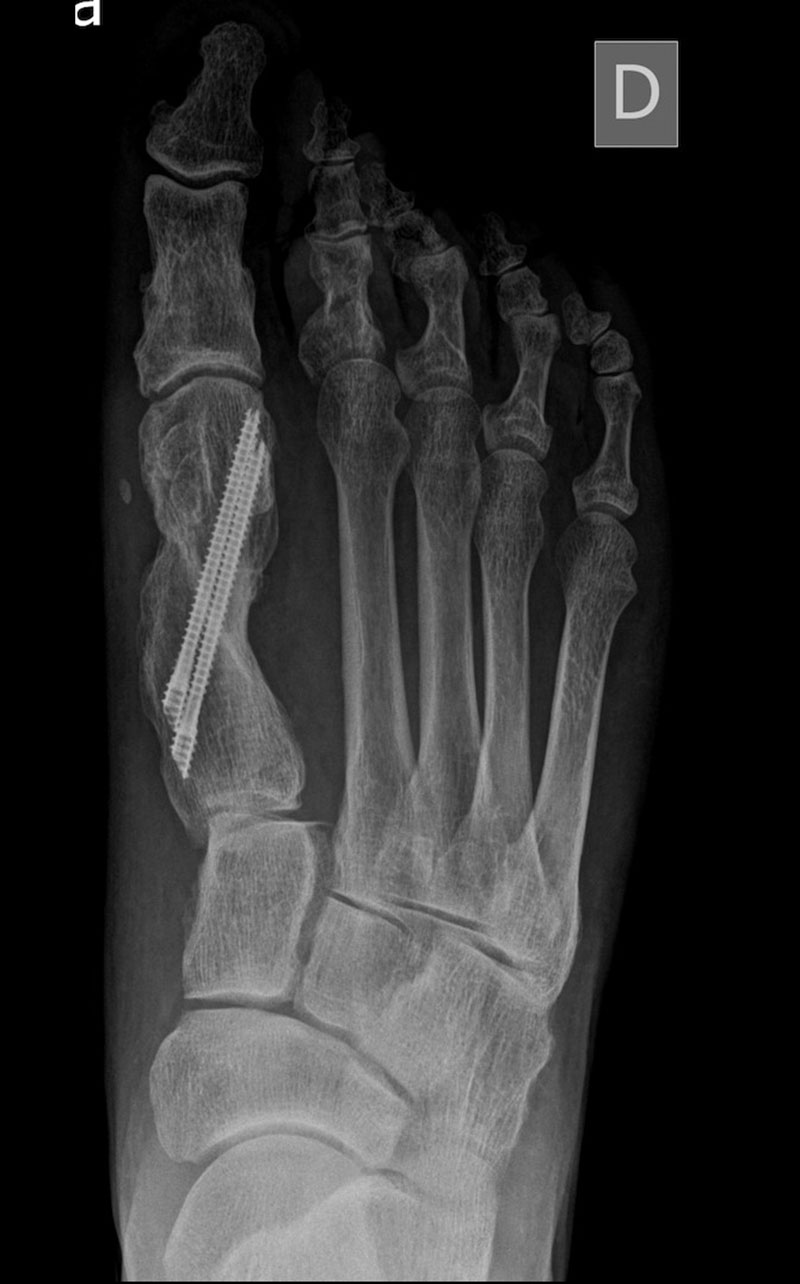

El caso que presentamos es muy representativo de la capacidad de corrección de la cirugía percutánea de tercera generación en la deformidad de Hallux Valgus. Se trata de una paciente con dolor a nivel del bunion y metatarsalgia con un 2º dedo sobre el primero que también le causa intolerancia con el calzado. Fue sometido a una técnica percutánea llamada MICA (Minimal Invasive Chevron Akin), sin ingreso y permitiendo carga inmediata

En las imágenes radiográficas se observa cómo se consigue una gran corrección en la posición de los dedos y una reducción de los sesamoideos sobre la cabeza metatarsiana. La fijación con tornillos nos va a permitir mantener esa reducción y estabilizar el montaje para reducir el dolor postoperatorio y permitir una buena consolidación ósea, como se ve en la última imagen.